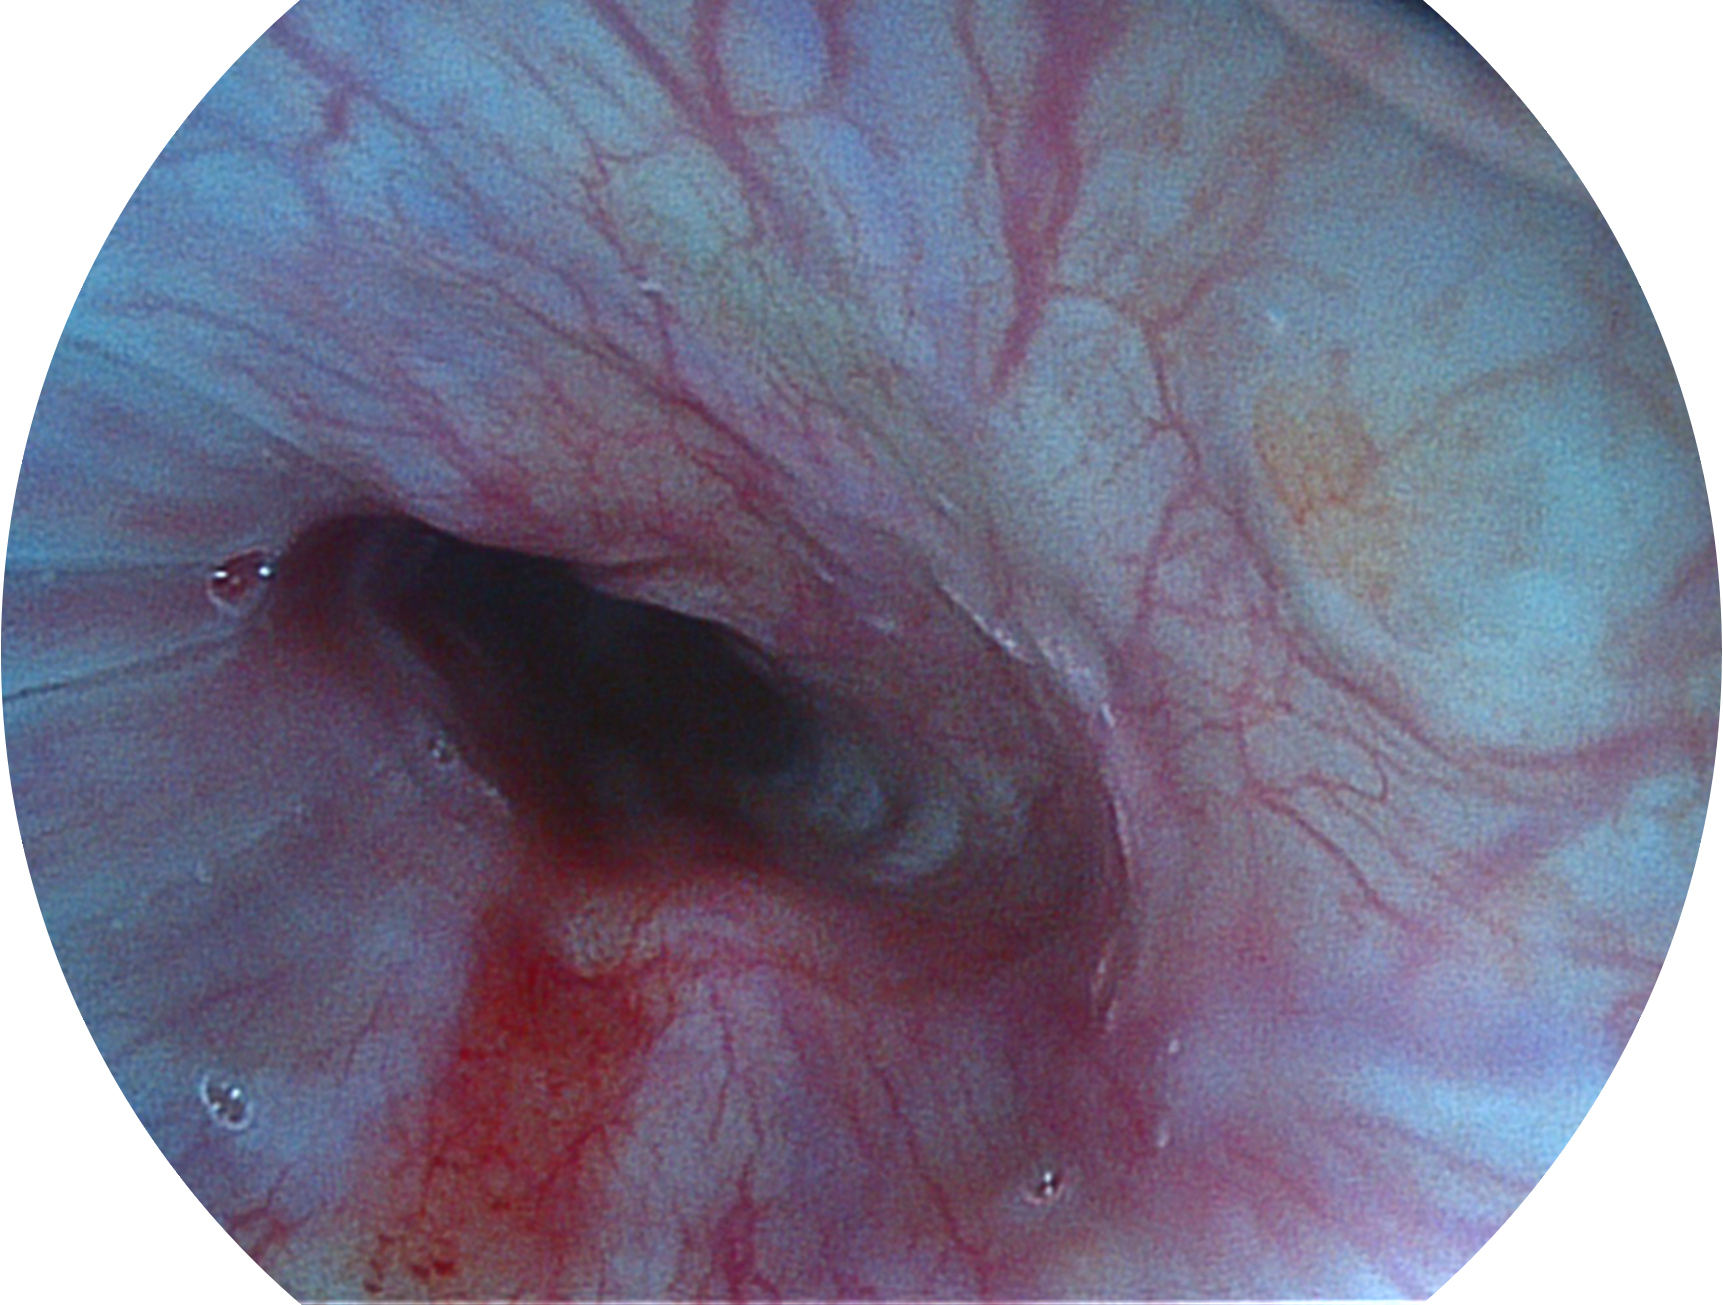

開立新開發(fā)的內(nèi)鏡染色技術(shù),主要是基于多波長(zhǎng)LED 光源的開發(fā),VLS-55Q 四波長(zhǎng)LED 光源是由四個(gè)不同顏色的LED光按照相應(yīng)照明模式所規(guī)定的特定發(fā)光比例進(jìn)行合束后形成,合束后形成的照明光的光譜由紅光、綠光、藍(lán)光及藍(lán)紫光這四個(gè)不同的波段范圍構(gòu)成。具有更高光譜自由度,通過(guò)光譜比例的控制,實(shí)現(xiàn)了聚譜成像技術(shù),英文全稱為“Spectral Focused Imaging, SFI”,縮寫為“SFI”和光電復(fù)合染色成像技術(shù),英文全稱為“Versatile Intelligent Staining Technology, VIST”,縮寫為“VIST”。